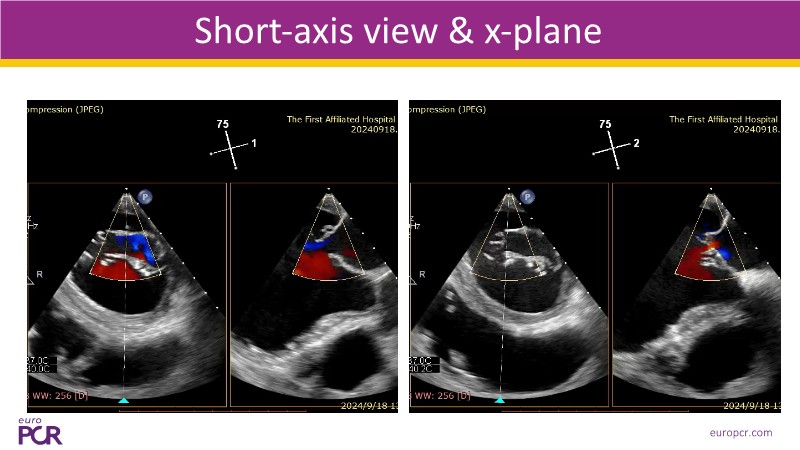

- To discover tips and techniques for mitral TEER in patients with challenging anatomy and difficult imaging